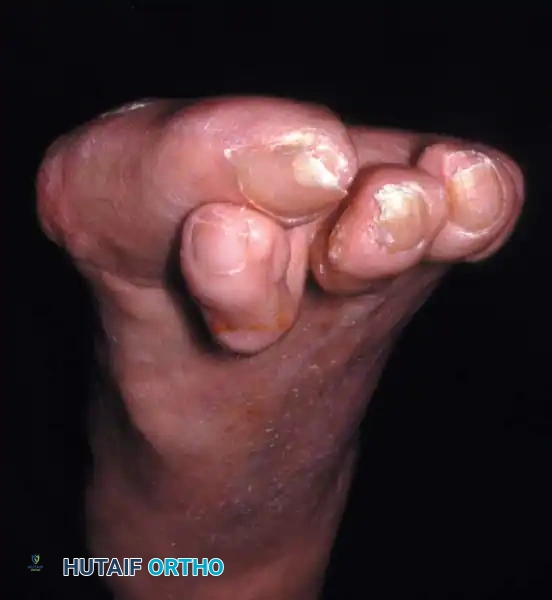

Hallux valgus (lateral deviation of the great toe) is not a single disorder, as the name implies, but a complex deformity of the fi rst ray that frequently is accompanied by deformity and symptoms in the lesser toes (Fig. 78-1). Often the angle between the fi rst and second metatarsals is more than the 8 to 9 degrees usually considered to be the upper limits of normal. The valgus angle of the fi rst metatarsophalangeal joint also is more than the 15 to 20 degrees considered to be the upper limits of normal (Fig. 78-2). If the valgus angle of the fi rst metatarsophalangeal joint exceeds 30 to 35 degrees, pronation of the great toe usually results. With this abnormal rotation, the abductor hallucis, which is normally plantar to the fl exion-extension axis of the fi rst metatarsophalangeal joint, moves further plantarward (Fig. 78-3). In this case, the only restraining medial structure is the medial capsular ligament with its capsulosesamoid portion (inserting into the base of the proximal phalanx) (Fig. 78-4) and capsulophalangeal portion (inserting into the plantar plate). The adductor hallucis, which is unopposed by the abductor hallucis, pulls the great toe further into valgus, stretching the medial capsular ligament (particularly the capsulosesamoid), attenuating this structure, and allowing the metatarsal head to drift medially from the sesamoids. In addition, the fl exor hallucis brevis, fl exor hallucis longus, adductor hallucis, and extensor hallucis longus increase the valgus moment at the metatarsophalangeal joint, further deforming the fi rst ray. The deep transverse intermetatarsal ligament runs between the plantar plates at the metatarsophalangeal joints and does not insert into bone on the adjacent sides of the metatarsal heads. Finally, the sesamoid ridge on the plantar surface of the fi rst metatarsal head (the crista) fl attens because of pressure (abutment) from the tibial sesamoid (Fig. 78-5). With this restraint lost, the fi bular sesamoid displaces partially or completely into the fi rst intermetatarsal space (see Fig. 78-2). In this situation, the patient is bearing less weight on the fi rst ray and more on the lesser metatarsal heads, increasing the likelihood of transfer metatarsalgia, callosities, and stress fracture of a lesser metatarsal.

a congruent metatarsophalangeal articulation; phalangeal osteotomy or distal metatarsal osteotomy, rather than tightening of the medial capsular repair, should be used for further correction. The valgus posture of the great toe frequently causes a hammer toe–like deformity of the second toe (Fig. 78-7). In addition, the splaying of the forefoot makes the wearing of shoes more diffi cult; with shoes that have a narrow toe box, corns often develop, as does bursal hypertrophy over the medial eminence of the fi rst metatarsal head (bunion). With valgus subluxation of the fi rst metatarsophalangeal joint, osteoarthritis frequently develops. In this case, the entire spectrum of hallux valgus is present: varus deformity of the fi rst metatarsal, valgus of the great toe, bunion formation, arthritis of the fi rst metatarsophalangeal joint, hammer toe of one or more toes, corns, calluses, and meta-

Keller Resection Arthroplasty The Keller procedure combines resection hemiarthroplasty of the fi rst metatarsophalangeal joint with removal of the medial eminence of the fi rst metatarsal (Fig. 78-28). Although removing the base of the proximal phalanx decompresses the joint and mobilizes the hallux, allowing marked correction of valgus, the varus of the fi rst metatarsal is not corrected, and maintaining correction of the valgus of the hallux is diffi cult. Other complications of the Keller procedure have been emphasized in the literature to such an extent (with neither the incidence nor the severity of such complications clearly documented) that the indications for this procedure have been limited severely. In our experience, however, complications are uncommon if patients are selected carefully. Modifi cations in the original technique also have allowed expansion of the indications for the Keller bunionectomy. Candidates for the Keller procedure are patients older than 50 years with moderate-to-severe hallux valgus (30 to 45 degrees); intermetatarsal angles of 13 degrees or less, indicating mild-to-moderate metatarsus primus varus; and pain over the medial eminence with any shoe worn, so the variety of shoes the patient can wear is severely limited. An incongruous fi rst metatarsophalangeal joint caused by

Fig. 78-26 Modifi ed McBride bunionectomy (DuVries; Mann). A, Medial capsule of second metatarsophalangeal joint is sutured to lateral capsule of fi rst metatarsophalangeal joint with interposition of released adductor hallucis. B, Medial capsular resection. C, Confi guration after capsular resection. D, After capsular imbrication, hallux should rest in neutral position or not exceed 5 degrees of varus. E, Postoperative dressing technique (Mann). ( E after Beverly Kessler; courtesy of LTI Medica and The Upjohn Company.) lateral subluxation of the phalanx on the metatarsal head, severe lateral displacement of the sesamoids, and any evidence of degenerative cartilage changes in the joint all are radiographic indications for the Keller procedure. Two modifi cations in technique can expand these indications, however, to include patients with more severe deformities (Fig. 78-29) (but not to include younger patients): fi bular sesamoidectomy and lateral displacement of the fi rst metatarsal. Using these modifi cations, Donley et al. obtained an average 18-degree correction of the metatarsophalangeal angle and an average 6-degree correction of the intermetatarsal angle in 38 patients (50 feet);

95% of patients were satisfi ed with their results. Patients with 50 degrees or more of valgus of the hallux (18 to 20 degrees of varus of the fi rst metatarsal), complete lateral dislocation of the sesamoids, marked degenerative changes, and severe pronation of the hallux may benefi t functionally and cosmetically from alterations of the standard technique.

Fig. 78-29 Severe hallux valgus with bursa formation in 70-year-old woman. A and B, Anteroposterior and lateral clinical photographs of patient’s right foot. C, Correction of deformity by modifi ed Keller procedure. D, Preoperative and postoperative weight bearing radiographs of same patient.